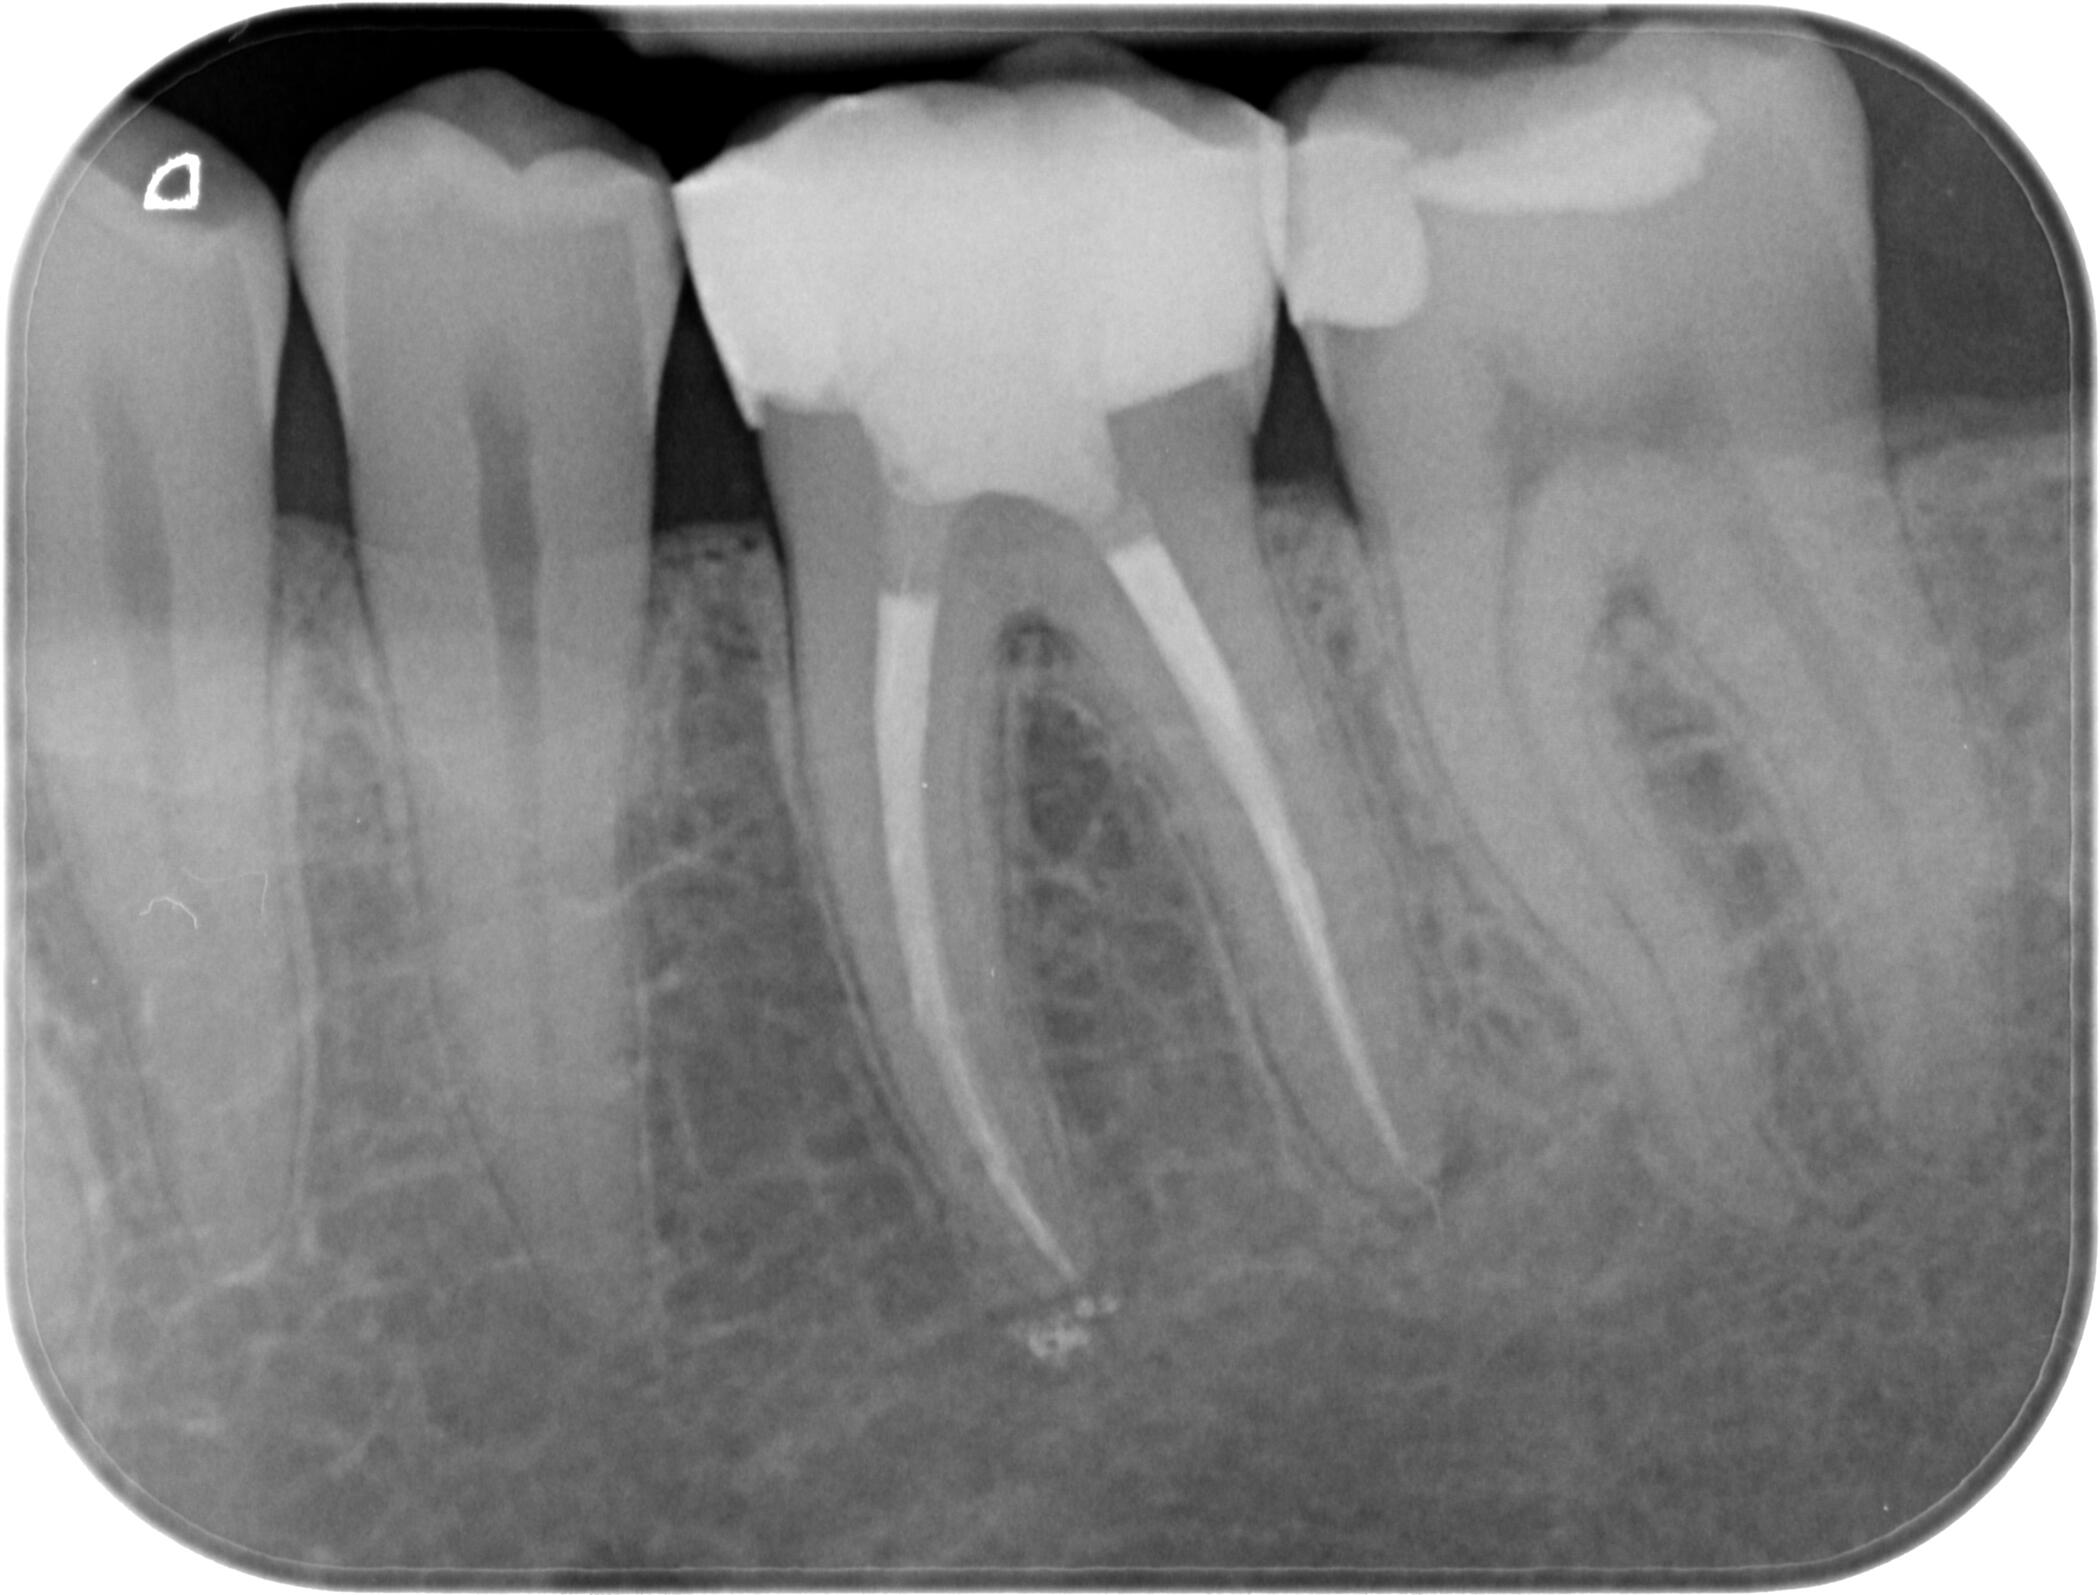

Периапикална / Сегментна рентгенография

Интраорален рентгенов апарат, характеризиращ се с бързо и лесно позициониране при изследване, за максимален комфорт на пациента.

За още по-голяма безопасност на пациентите, интраоралният ни рентген е оборудван и със специален тубус, който фокусира рентгеновите лъчи само в мястото, което искаме да бъде диагностицирано!